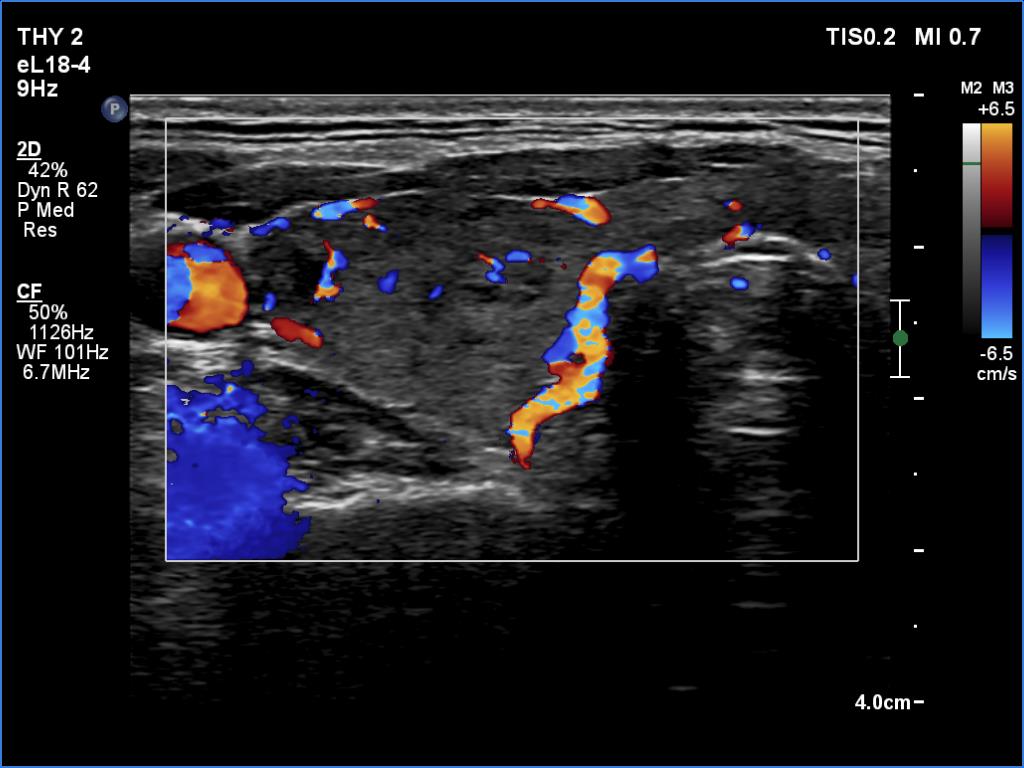

Right lobe, longitudinal scan

Left lobe, color Doppler mode